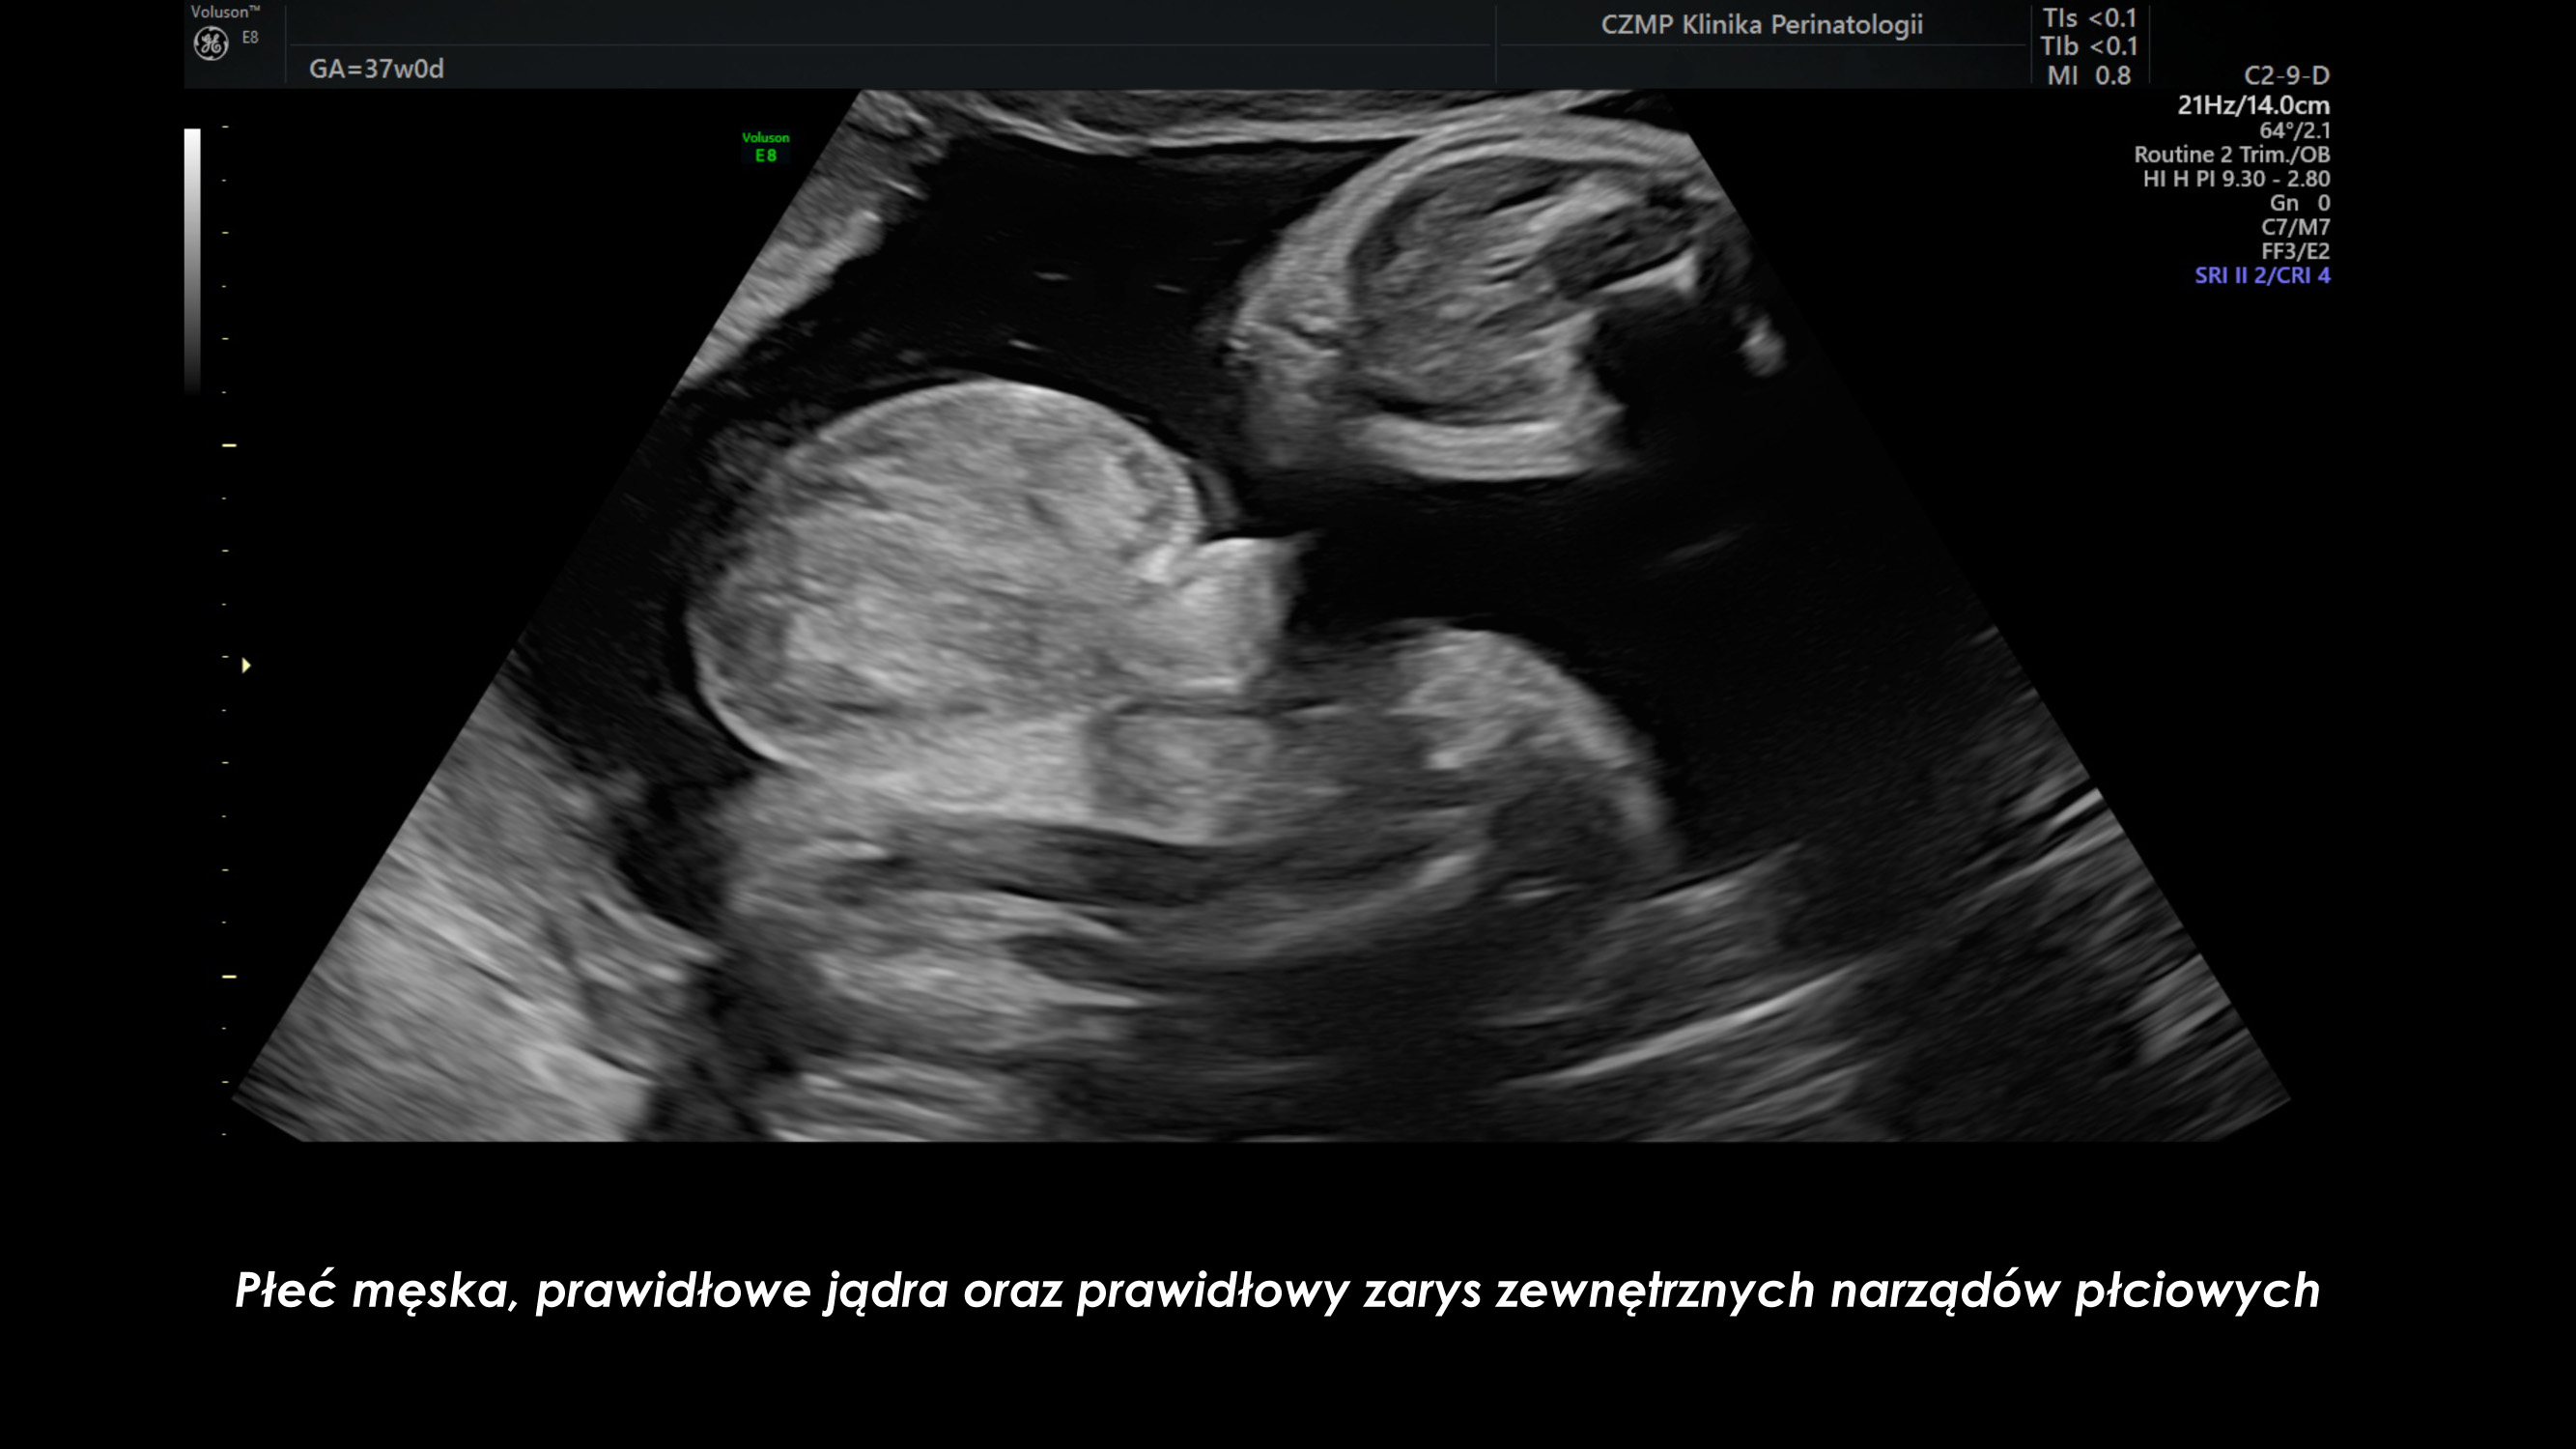

Nietypowy guz jamy brzusznej płodu